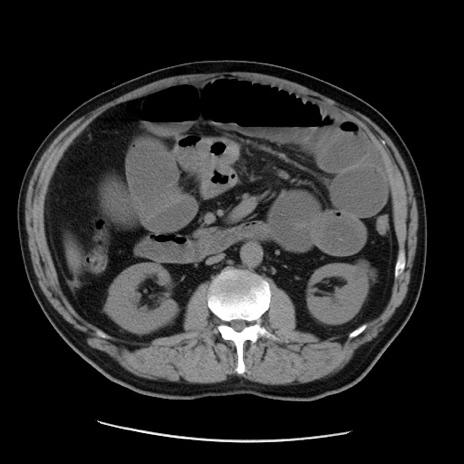

症例20(横断像)

【症例】 60歳代男性

【主訴】 腹部膨満、嘔吐

【現病歴】5日前頃より倦怠感を認め食事量減少し4日前の朝嘔吐、食事摂取困難となった。 3日前近医受診し点滴施行され整腸剤などを処方された。 当日他院を受診し、腹部膨満著明、炎症反応の上昇(CRP10.8、WBC11200)あり、紹介受診となる。

【身体所見】 意識JCS1 受け答えがはっきりしないBP 111/57mHg、 P 67bpm、、BT35.2°C、SpO2 97%(RA)、 腹部:膨隆、打診で鼓音あり、全体的に圧痛有り、腸蠕動音(-)、反跳痛ははっきりせず。

【データ】WBC 11400、CRP 14.20